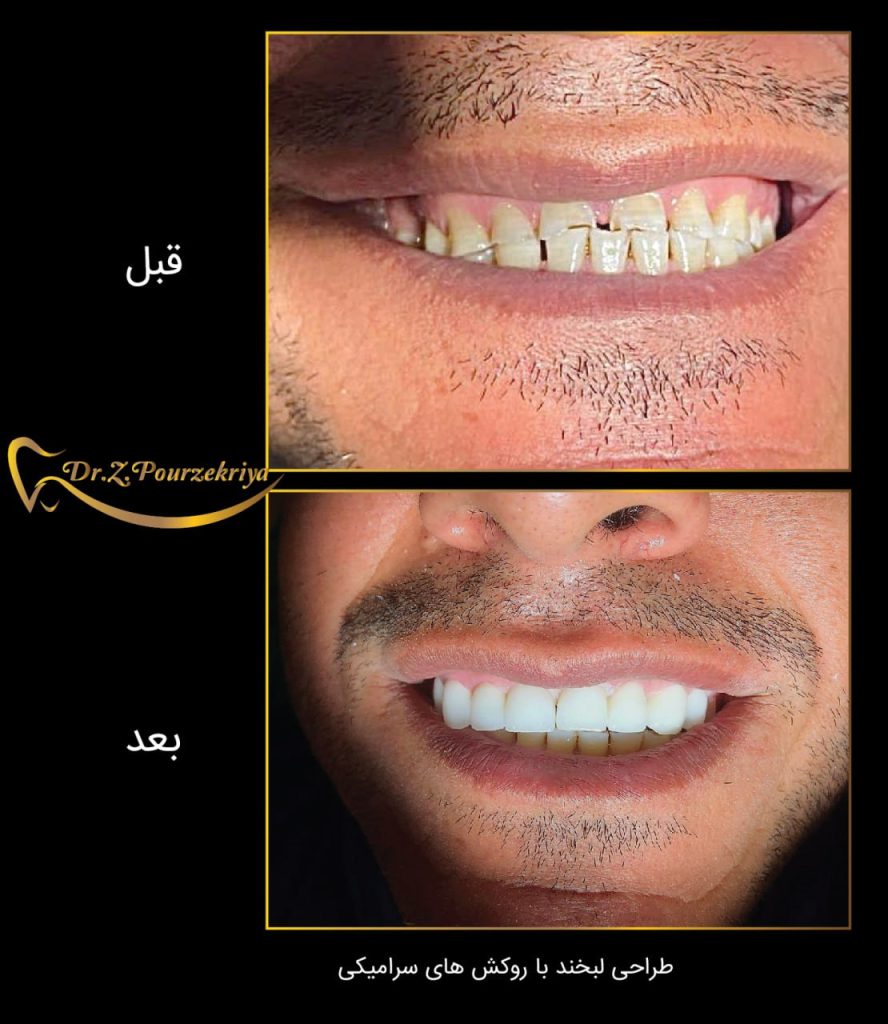

روکش های سرامیکی دندان

با ماندگاری طولانی

دندان های درخشان لبخندی منحصر به فرد

روکش های سرامیکی دندان

با ماندگاری طولانی

نمونه های درمان

دکتر زکیه پور ذکریا، جراح دندانپزشک و ایمپلنتولوژیست :

ورضایت مراجعین برایم بزرگترین تبلیغ محسوب میشود